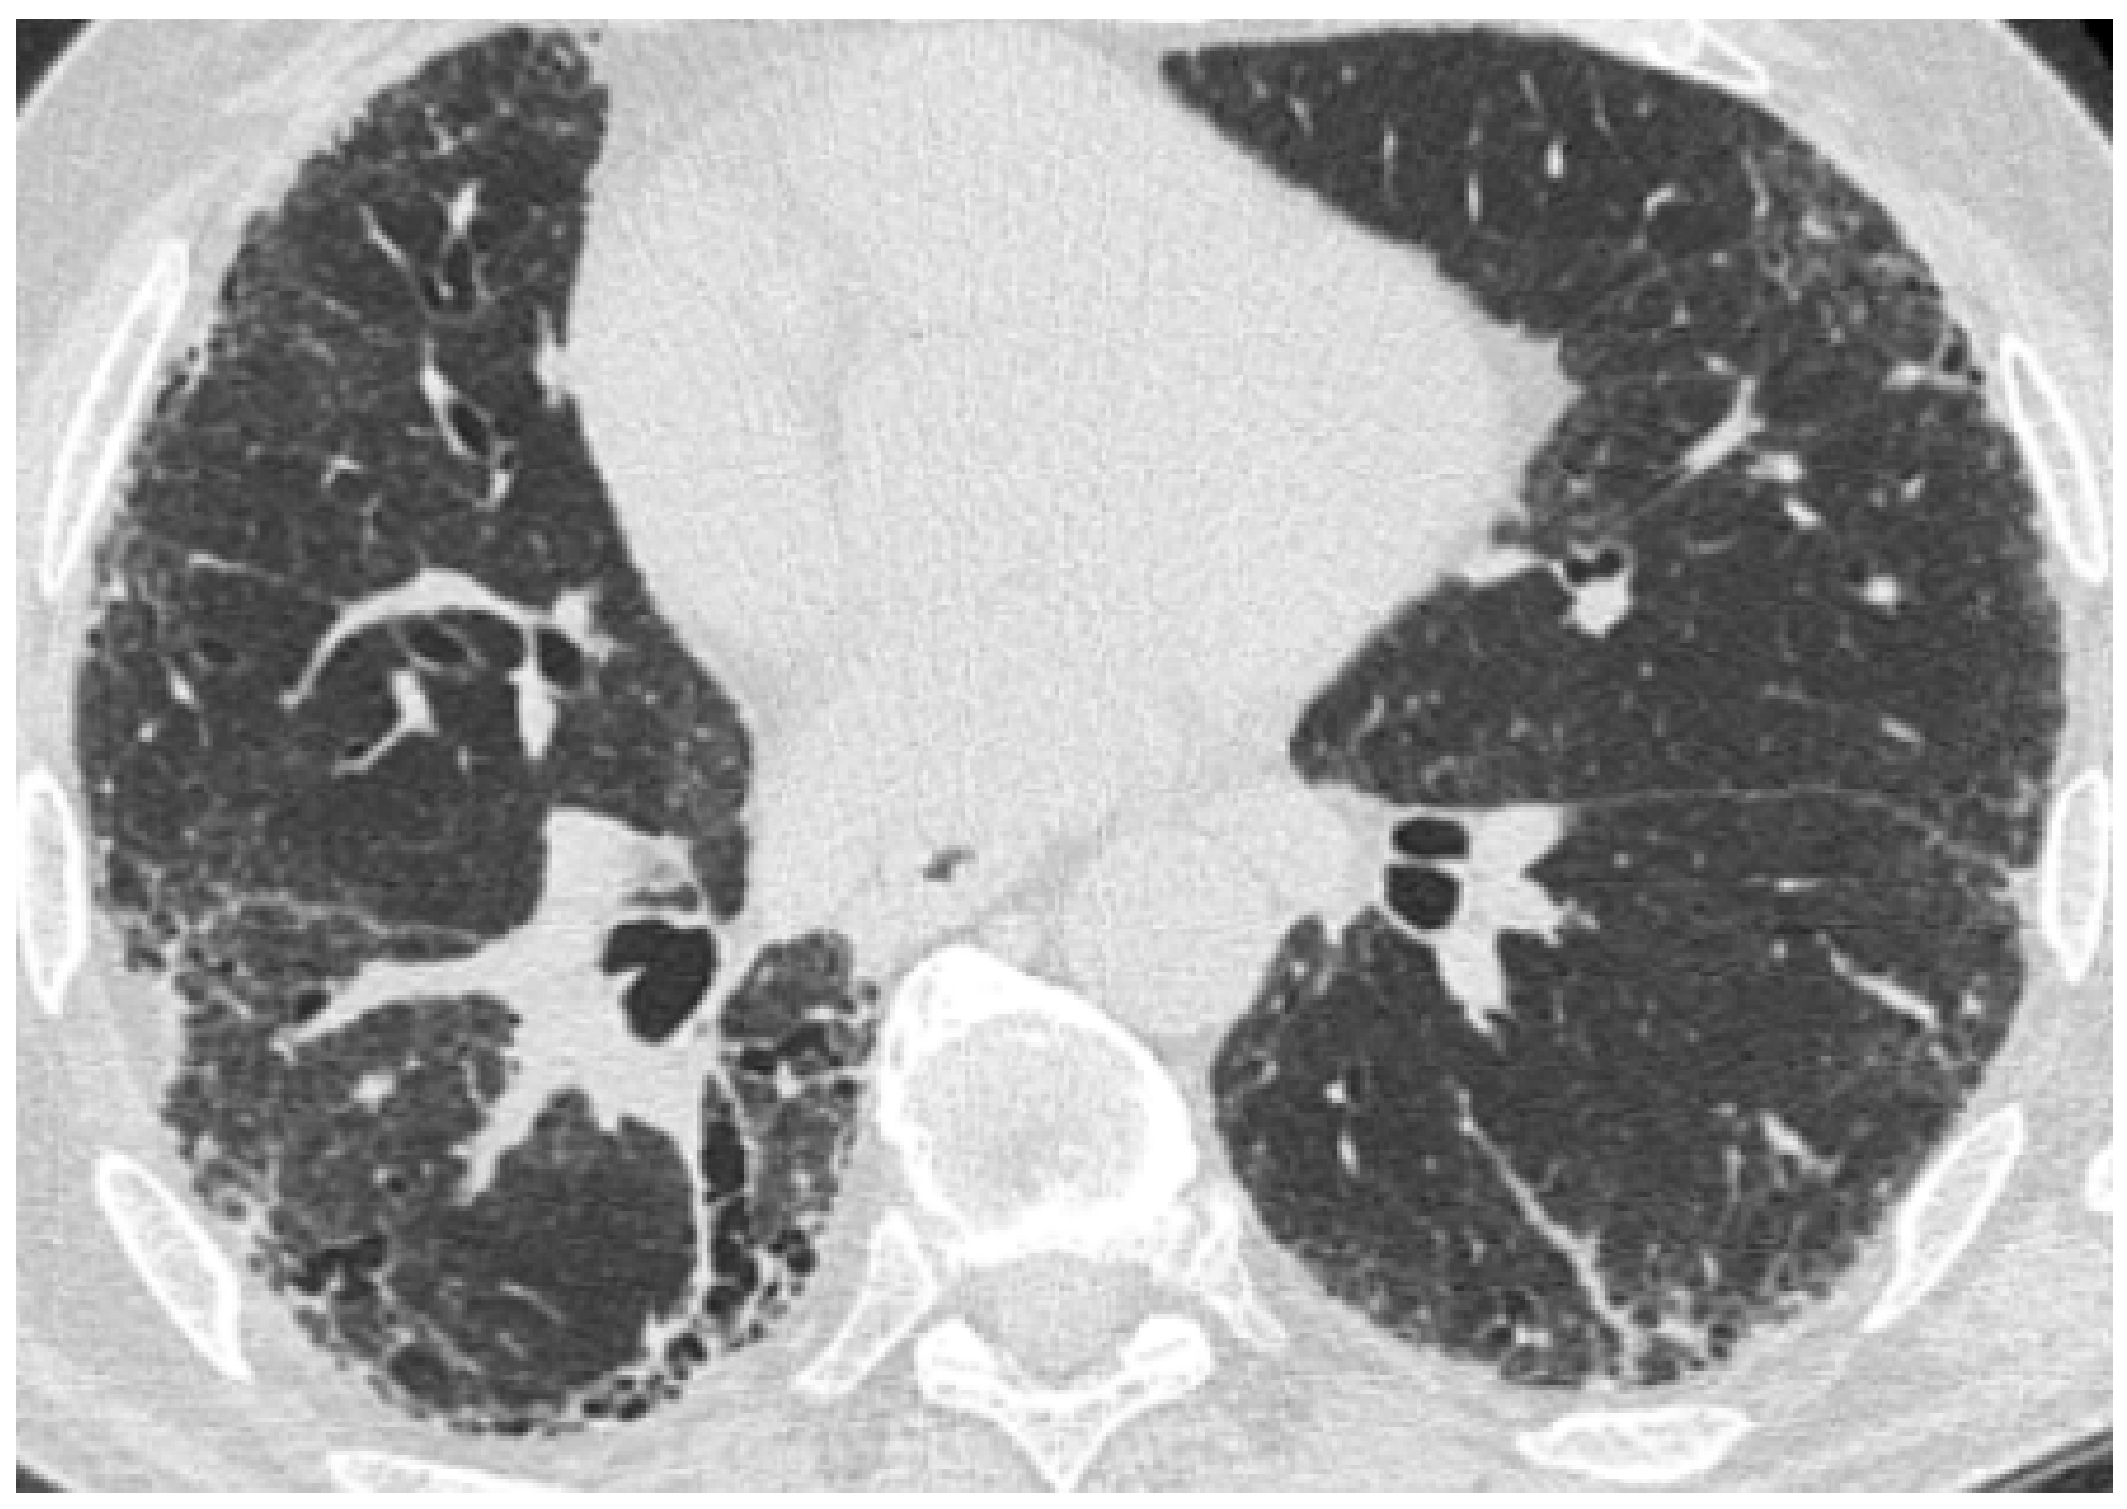

| Acute exacerbation IPF | New bilateral ground glass opacities and/or consolidation on a background of reticular or honeycombing pattern. | ||